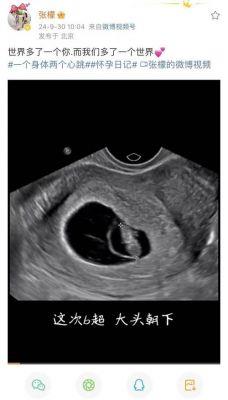

此次怀孕的消息,在9月最后一天的公布,透露出这对夫妻的激动心情。对于张檬和金圣恩来说,怀孕将是他们人生中一个重要的里程碑。虽然之前有些困难,但终于在上天的眷顾下,他们迎来了属于自己的孩子。两人都表达了对未来生活的美好期待,似乎已经在心中描绘了一个温馨的家庭画面。